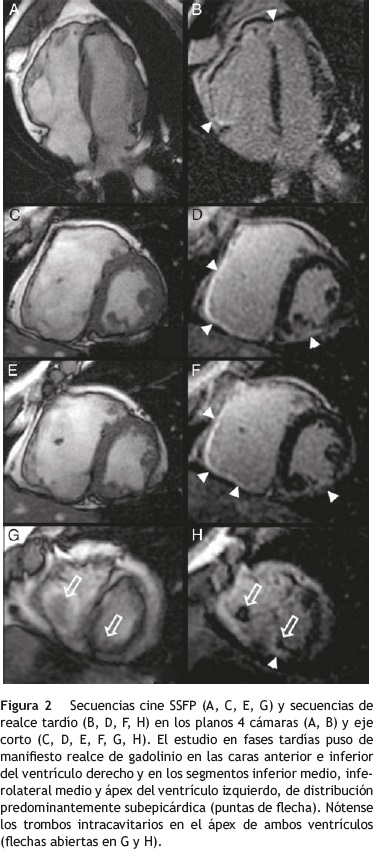

El estudio de CRM se llevó a cabo con un protocolo convencional que incluía secuencias anatómicas del tórax, secuencias cine eco de gradiente steady-state free precession (SSFP) en los planos 4 cámaras, eje corto y tracto de salida del ventrículo izquierdo, perfusión en reposo y secuencias de realce precoz y realce tardío tras la administración intravenosa de contraste paramagnético3. La CRM puso de manifiesto un ventrículo izquierdo de tamaño

normal con disfunción sistólica moderada (FE = 35%), acinesia del segmento inferior medio y discinesia y abombamiento diastólico del segmento inferolateral medio. Los grosores miocárdicos eran normales excepto en el segmento inferolateral medio, que se encontraba muy adelgazado (6mm). La pared lateral del ventrículo izquierdo mostraba una morfología irregular y se encontraba infiltrada por tejido adiposo (fig. 1). El ventrículo derecho estaba dilatado (volumen telediastólico ajustado por superficie corporal de 147ml/m2, volumen telesistólico ajustado por superficie corporal de 111 ml/m2) y presentaba una función sistó-lica severamente deprimida (FE = 25%). Morfológicamente había áreas de adelgazamiento de la pared. El análisis de la contractilidad segmentaria de este ventrículo mostró movimiento disincronía del septum, disincronía de la contracción ventricular, segmentos acinéticos y discinéticos y formación de pequenñas saculaciones/aneurismas (fig. 1). Durante la perfusión en reposo se observaron trombos endocavitarios en los ápices de ambos ventrículos. En fases tardías se objetivó realce de las caras anterior e inferior del ventrículo derecho y de los segmentos inferior medio, inferolateral medio y ápex del ventrículo izquierdo, con una distribución predominantemente sube-picárdica (fig. 2). Ante estos hallazgos, el estudio de CRM se consideró compatible con miocardiopatía arritmogénica del ventrículo derecho con afectación del ventrículo izquierdo.